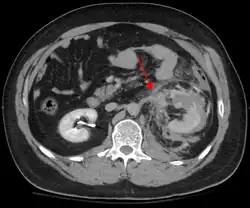

Radiografia mostrando uma fratura dos ramos púbicos inferior e superior em um paciente com artroplastias de quadril anteriores

FractureRtSandIRami(Sin2).png